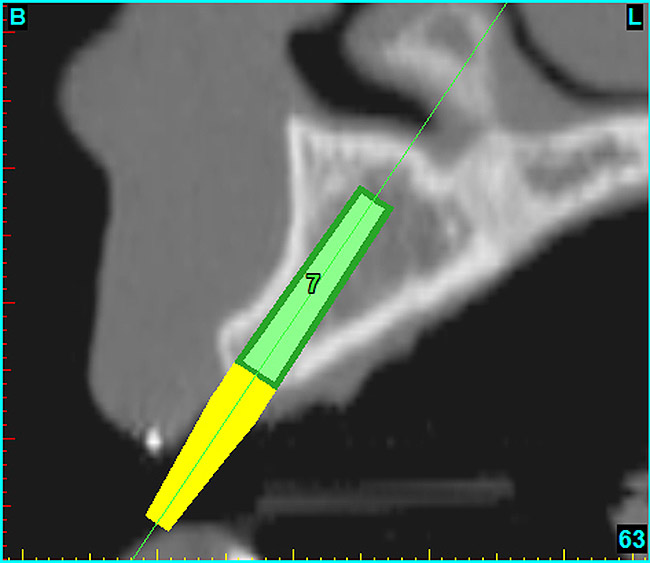

After the basic plan had been established, it was re-evaluated using interactive 3D images. The reconstructed 3D view of the maxilla clearly illustrated the extent of the bilateral facial concavities, and the root eminences of the adjacent and posterior teeth (Figure 7A). The placement of the virtual implants then was evaluated to ensure that the facial cortical plate was not perforated (Figure 7B). The implants were labeled individually as “7” and “10,” with the simulated yellow abutment projection indicating the facial-lingual inclination through the bone to the level above the incisal edge of adjacent teeth. The ability to gain a better understanding of these individual root forms can not be underestimated. The dental literature has suggested certain parameters for placing implants near teeth and implants next to other implants. However, there is little scientific 3D documentation to support these suggested rules.5-10 The use of an interactive treatment-planning software application permits closer scrutiny of previously difficult-to-visualize areas, and can now be used to redefine perceptions of spatial positioning of implants, especially when in close proximity to natural tooth roots, vital anatomy, and adjacent implants.27-29

Figure 7a  The 3D reconstruction showed (A) the facial concavities and root eminences, and allowed (B) for evaluation of virtual implant placement to ensure the facial cortical plate was not perforated.

Figure 7a

Figure 7b  The 3D reconstruction showed (A) the facial concavities and root eminences, and allowed (B) for evaluation of virtual implant placement to ensure the facial cortical plate was not perforated.

Figure 7b